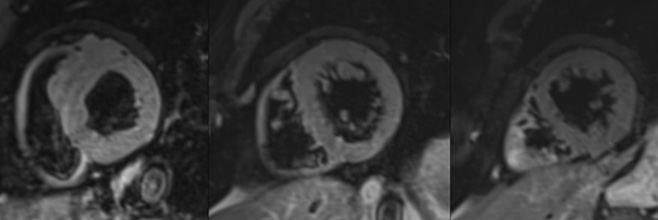

CAZ: Cardiomiopatia dilatativa